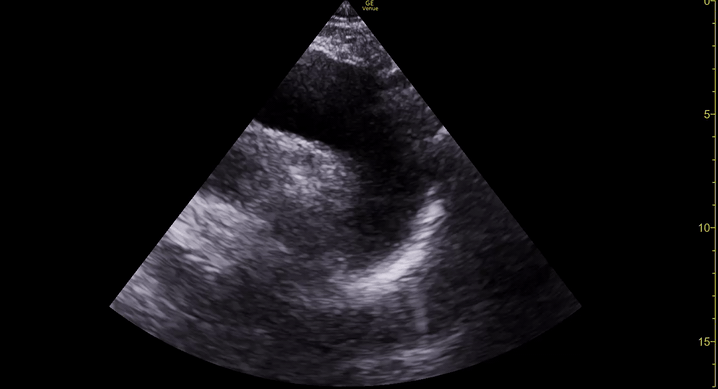

THE VIEWS

The subxiphoid view is the most reliable for detecting pericardial effusion. Still, it is ideal to obtain different views not to miss a focal effusion as small amounts of fluid can lead to tamponade physiology. Tamponade does not link strictly to the size of the effusion, but correlates more with the speed of onset, causes, and haemodynamic effects.

PITFALLS & PLEURAL EFFUSIONS

A common error is to confuse a pericardial fat pad with effusion. Fatty tissue has a heterogeneous echotexture, moving in coordination with the myocardium, and it cannot be tracked around the heart, especially posteriorly and to the apex. Another pitfall is misinterpreting a pleural effusion as a pericardial effusion. However, they can be differentiated by their relationship to the descending aorta. Pericardial effusion may be seen between the aorta and the LV free wall, whereas pleural effusions are posterior to the descending aorta. Lastly, other causes, namely hypovolaemia and large pleural effusions, can cause RA and RV collapse.

CARDIAC TAMPONADE

Progressively rising pressure translates into evolving tamponade, and this accompanies a series of ultrasound findings:

Initially, the RA collapses during ventricular systole (closed AV valves).

Followed by RV collapse in ventricular diastole (open AV valves).

Ultimately leading to LV collapse.

In addition, the presence of a non-collapsible, plethoric IVC is one of the most sensitive signs of tamponade, and a finding easy to visualise. Conversely, a pericardial effusion in a haemodynamically stable patient with a collapsible IVC is unlikely to represent tamponade.